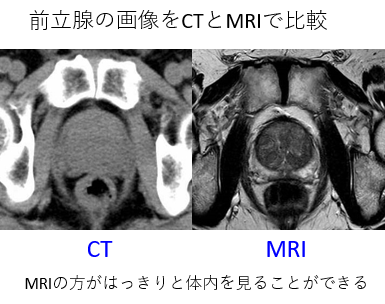

・がんや正常組織がCTよりもはっきり見える。

・治療の効果もCTよりよくわかる。